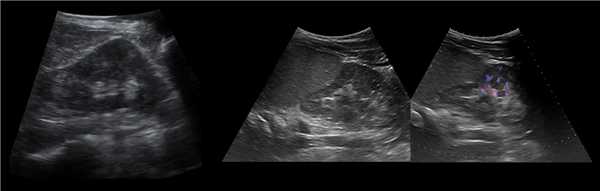

Трансплантированная почка обычно располагается вдоль поверхности подвздошнопоясничной мышцы, ее эхогенность совпадает с эхо- генностью обычной почки. Эхографические признаки отторжения трансплантата включают: патологическое увеличение размеров почки, гидронефроз, паранефральное скопление жидкости, гематомы, абсцессы и экстраренальные накопления мочи. При допплерографии почечного кровотока обычно определяется увеличение сосудистого сопротивления или полное прекращение кровотока в главной почечной артерии, междолевых артериях, дугообразных артериях (для исключения отторжения), почечной вене (для исключения перегиба почечной вены).

Способ диагностики острого отторжения пересаженной почки

Способ диагностики острого отторжения пересаженной почки путем определения в послеоперационном периоде индекса периферического сопротивления сосудистого русла трансплантата при допплеросонографии и, дополнительно, эхосканировании, определяют объем трансплантата, толщину его паренхимы, индекс примамид мозгового вещества,а индекс периферического сопротивления сосудистого русла пересаженной почки определяют по отношению разницы максимального пикового систолического допплеровского частотного сдвига в конце диастолы к максимальному пиковому систолическому допплеровскому частотному сдвигу и при индексе периферического сопротивления сосудистого русла пересаженной почки более 0,79, или объеме почки более 300 см3, или толщине паренхимы более 2 см и индексе пирамид мозгового вещества более 2,1, или толщине паренхимы меньше или равной 2,0 см и индексе пирамид мозгового вещества более 2,8 диагностируют острое отторжение пересаженной почки (Арутюнян С. М. и соавт., 1990).

Способ диагностики острого отторжения пересаженной почки путем определения в послеоперационном периоде индекса периферического сопротивления сосудистого русла трансплантата при допплеро- сонографии и, дополнительно, эхосканировании, определяют объем трансплантата, толщину его паренхимы, индекс примамид мозгового вещества,а индекс периферического сопротивления сосудистого русла пересаженной почки определяют по отношению разницы максимального пикового систолического допплеровского частотного сдвига в конце диастолы к максимальному пиковому систолическому допплеровскому частотному сдвигу и при индексе периферического сопротивления сосудистого русла пересаженной почки более 0,79, или объеме почки более 300 см3, или толщине паренхимы более 2 см и индексе пирамид мозгового вещества более 2,1, или толщине паренхимы меньше или равной 2,0 см и индексе пирамид мозгового вещества более 2,8 диагностируют острое отторжение пересаженной почки (Арутюнян С. М. и соавт., 1990).